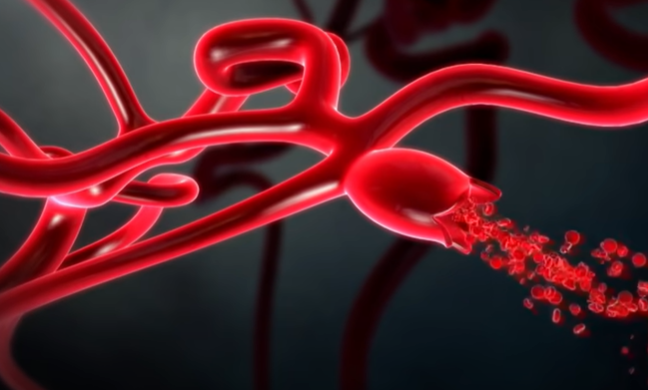

뇌동맥류

약해진 혈관 벽이 늘어나 마치 꽈리 모양으로 부풀어 오른 뇌동맥류는 터지는 순간 극심한 두통을 유발한다.

가장 위험한 게 뇌동맥류 파열에 의한 지주막하 출혈이다. 처음 출혈이 생기고 두통이 어느 정도 해소된 다음에는 환자가 마치 병이 나은 것처럼 생각하는데 만약 뇌동맥류가 터진 상태로 출혈이 멈추지 않으면 급사를 하게 된다.

뇌에 있는 동맥은 지주막하 공간이라는 뇌척수액이 가득 차 있는 곳에 있어서 마치 물에 동맥이 떠 있는 형태이다. 그곳에 있는 동맥류에 꽈리가 생겨서 파열되면 뇌 전체로 피가 퍼지기에 순식간에 뇌압을 상승시킨다. 뇌동맥류가 터지는 정도에 따라서 임상적으로 등급을 나누는데 한두 시간 정도 참을 수 있을 정도의 가벼운 두통부터 급사하는 정도까지, 출혈량이나 파열 정도에 따라 다양한 임상 증상이 생긴다.

뇌동맥류 증상, 형태

아래 사진의 특정 환자의 경우, 모두 6개의 뇌동맥류가 자리 잡고 있었다. 뇌동맥류는 터지기 전에는 별다른 증상이 없지만 크기가 클 경우 두통을 일으키기도 한다.

뇌동맥류의 크기가 가장 중요하다. 과거에는 10mm 이상의 뇌동맥류를 큰 동맥류라 했는데, 지금은 가장 긴 직경이 7mm 이상 되는 크기면 위험하다고 한다. 또한, 모양도 중요한데 밋밋하고 평평하게 생긴 뇌동맥류는 파열 위험성이 적으나, 매끈한 표면이 아닌 불룩한 형태의 울퉁불퉁한 형태나 뾰족한 뇌동맥류는 위험할 수 있다. 혈압이 높거나, 흠 연하는 경우, 여성이나 고령의 환자는 뇌동맥류가 커질 확률이 크다.